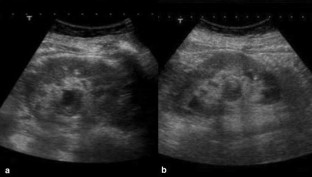

A 40-year-old woman was referred to our department for further investigation of a renal mass identified at an ultrasound (US) examination carried out in a private clinic because of abdominal pain. The mass was oval and hypoechoic, measured about 20 mm in diameter and was located near the left renal sinus; color Doppler showed peripheral blood flow. US examination carried out in our department using different equipment confirmed the presence of the mass but revealed intralesional blood flow suggesting aneurysm. This diagnosis was confirmed at subsequent computed tomography (CT) scanning and magnetic resonance imaging (MRI). The patient refused to undergo surgery and she is currently being monitored and has suffered no sequelae.

Fig. 1